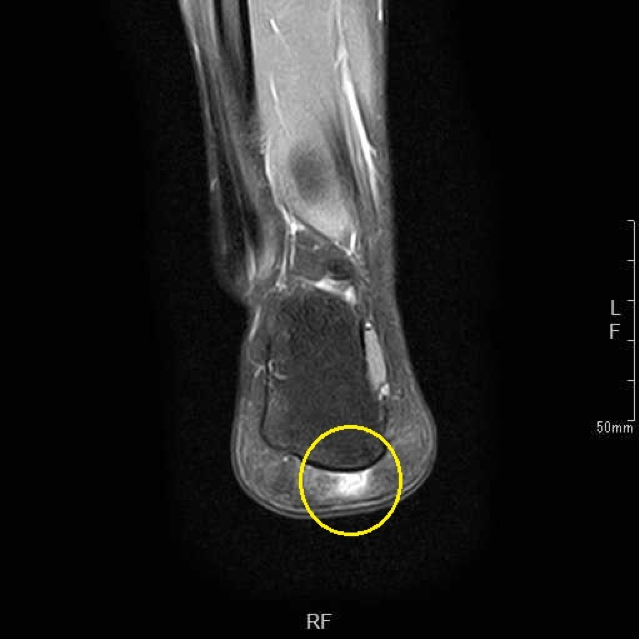

保存的治療で十分な改善が見られなかったため、より詳しく状態を調べるためにMRI検査を実施しました。その結果、足底腱膜の付着部(踵の骨にくっついている部分)と、その周囲の脂肪組織に変性(組織の質が変わってしまうこと)が認められました。

1ヶ月間の保存的治療で日常歩行は可能になりましたが、素足での痛みが残存していました。MRI検査で足底腱膜の付着部と脂肪組織の変性を認めたため、このような慢性的な変性に対しては体外衝撃波治療が効果を示す可能性があるという報告に基づき、治療をご提案しました。